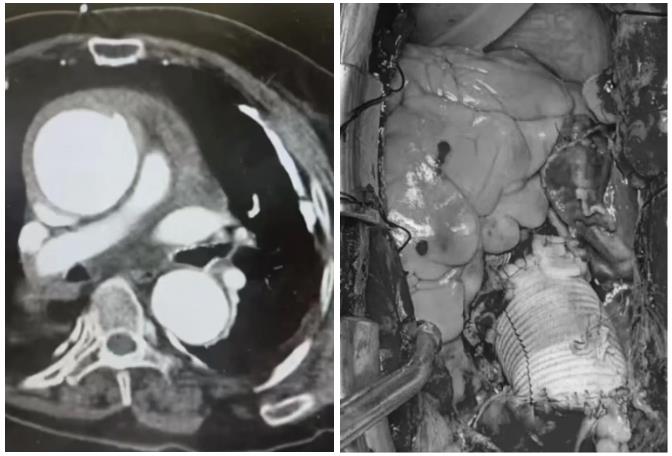

10:30,80岁的高龄患者拜某某,因突发意识障碍20分钟,由120送至我院急诊,入科后予以完善相关辅助检查,急查心电图示:窦速。血气分析示:酸中毒,高血糖,电解质紊乱。抢救过程中患者出现双侧血压下降,意识障碍,抢救团队立即密切配合完善头颅+胸部+腹部CT:考虑升主动脉瘤破裂伴心包填塞。病情凶险,随时存在生命危险,席主任立即调集120团队并及时联系上级医院团队紧急手术治疗,在所有人的努力下患者转危为安。